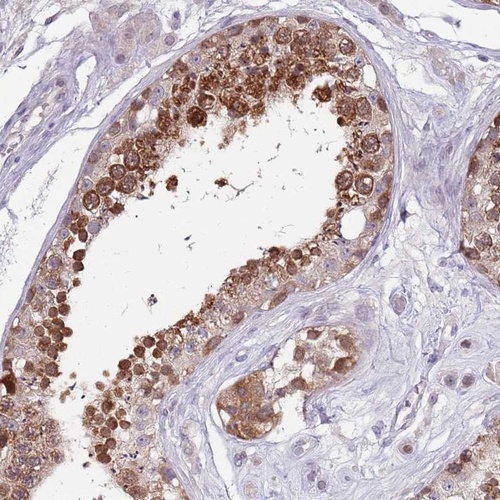

Immunohistochemical staining of human testis shows strong cytoplasmic positivity in cells in seminiferus ducts.